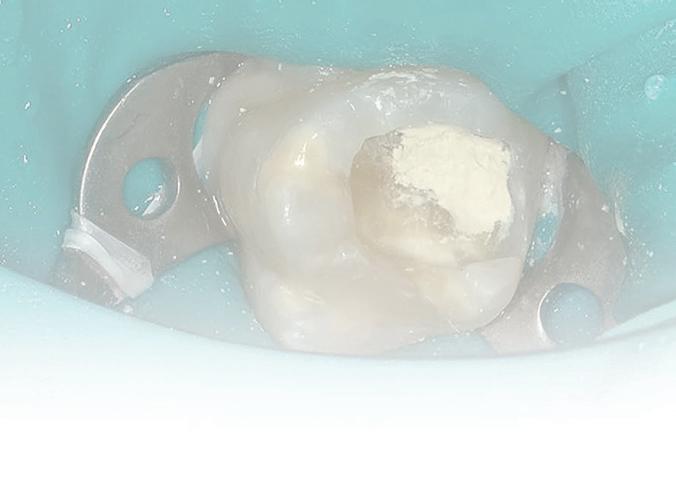

Knowing your own practice.

Often sales processes reveal that dentists have not understood their strengths and weaknesses and expose themselves to shocks during the selling process. Most accountants simply churn out tax returns for a variety of small businesses and individuals with no idea regarding how a dental practice compares with key benchmarks. These accountants are inadequate in representing their dental clients if a sale process reveals weakness whereas their client had assumed that they would have been advised by their accountant of issues that they should have addressed long before listing for sale.

Practice managers negative impact on profit and sale price.

Unfortunately, most practice managers —other than courtesy titles given to experienced receptionists—are profit destroyers rather than profit enhancers.

“Innocent” asked for a practice valuation and was shocked at the low figure. He sought deeper analysis and I pointed out that his non-clinical staff cost as a percentage of practice fees was extraordinarily high. With superannuation and work cover insurance, the “manager” was costing his practice $110,000 per year—and this was quite a few years back. The remainder of the non-clinical staff together cost as much as the average of all dental practices. The manager was not saving on other staff and her cost effectively reduced the capital value of his practice by around $400,000. He took a deep look at what the manager actually did and found out that with the assistance of a visiting bookkeeper and a bit of tightening of dental patient appointments and chairside assistants’ hours, he could dispense with the manager, reducing non-clinical staff overhead by $110,000. The practice manager’s position had long been redundant. A couple of years later he was able to sell his significantly more profitable practice for its true value.

Preparing to buy a dental practice.

The first thing to understand is that the vast majority of accountants and financial advisers know “diddly squat” about the differences between good and mediocre dental practices.

If they do have one or two dental clients, their interaction is invariably limited to completing annual tax and financial returns, but they are clueless as to how their clients’ practices compare with wellperformed practices or what to advise a buyer to look for beyond averaging the last three years’ profits.